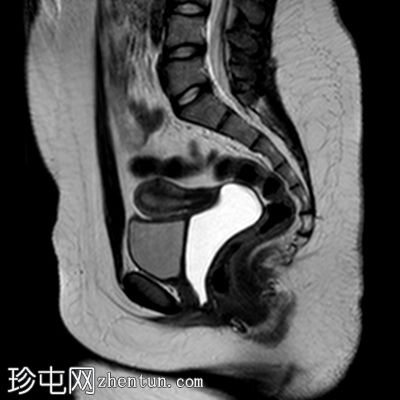

矢状位

T2加权像

阴道明显扩张,T1加权像呈中高信号,T2加权像呈高信号,耻骨联合下方可见一小局灶性隆起。

子宫大小正常,分区解剖结构正常。宫颈MRI表现正常。